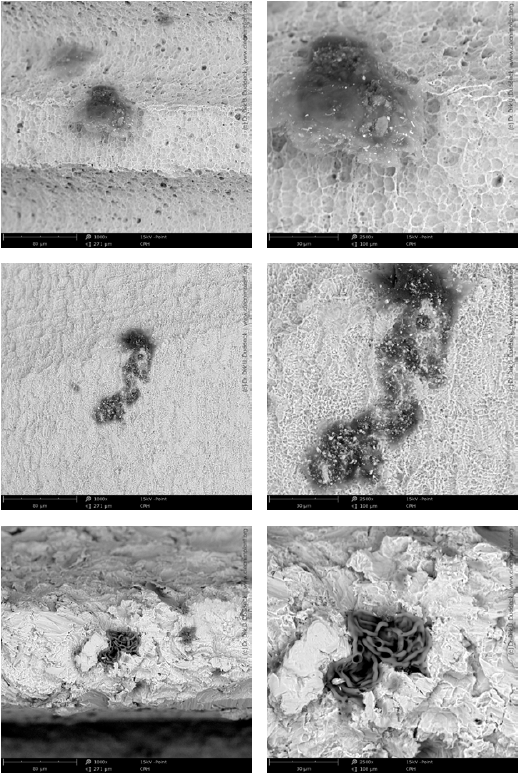

飛納臺(tái)式掃描電鏡使 Duddeck 博士能夠了解他的樣品并對(duì)其進(jìn)行更詳細(xì)的分析。它有助于在微米級(jí)別上分析樣本,深入研究患者在植入后必須面對(duì)的生物學(xué)影響。飛納電鏡的另一個(gè)特點(diǎn)是它為 Duddeck 博士和他的團(tuán)隊(duì)提供了材料襯度對(duì)比圖像,這對(duì)他們的研究至關(guān)重要。“我們現(xiàn)在可以立即看到植入物的材料襯度對(duì)比,直接識(shí)別出不是核心材料的鈦或氧化鋯的異物,黑點(diǎn)是有機(jī)污染物的跡象,亮點(diǎn)源于金屬殘留物,如鎳、銅、錫或鉻——肯定不會(huì)出現(xiàn)在可植入醫(yī)療設(shè)備上。我們可以用 EDS 進(jìn)一步分析這些顆粒,知道顆粒成分?!?/span>

飛納電鏡拍攝的無菌植入物上的有機(jī)污染 SEM 圖像